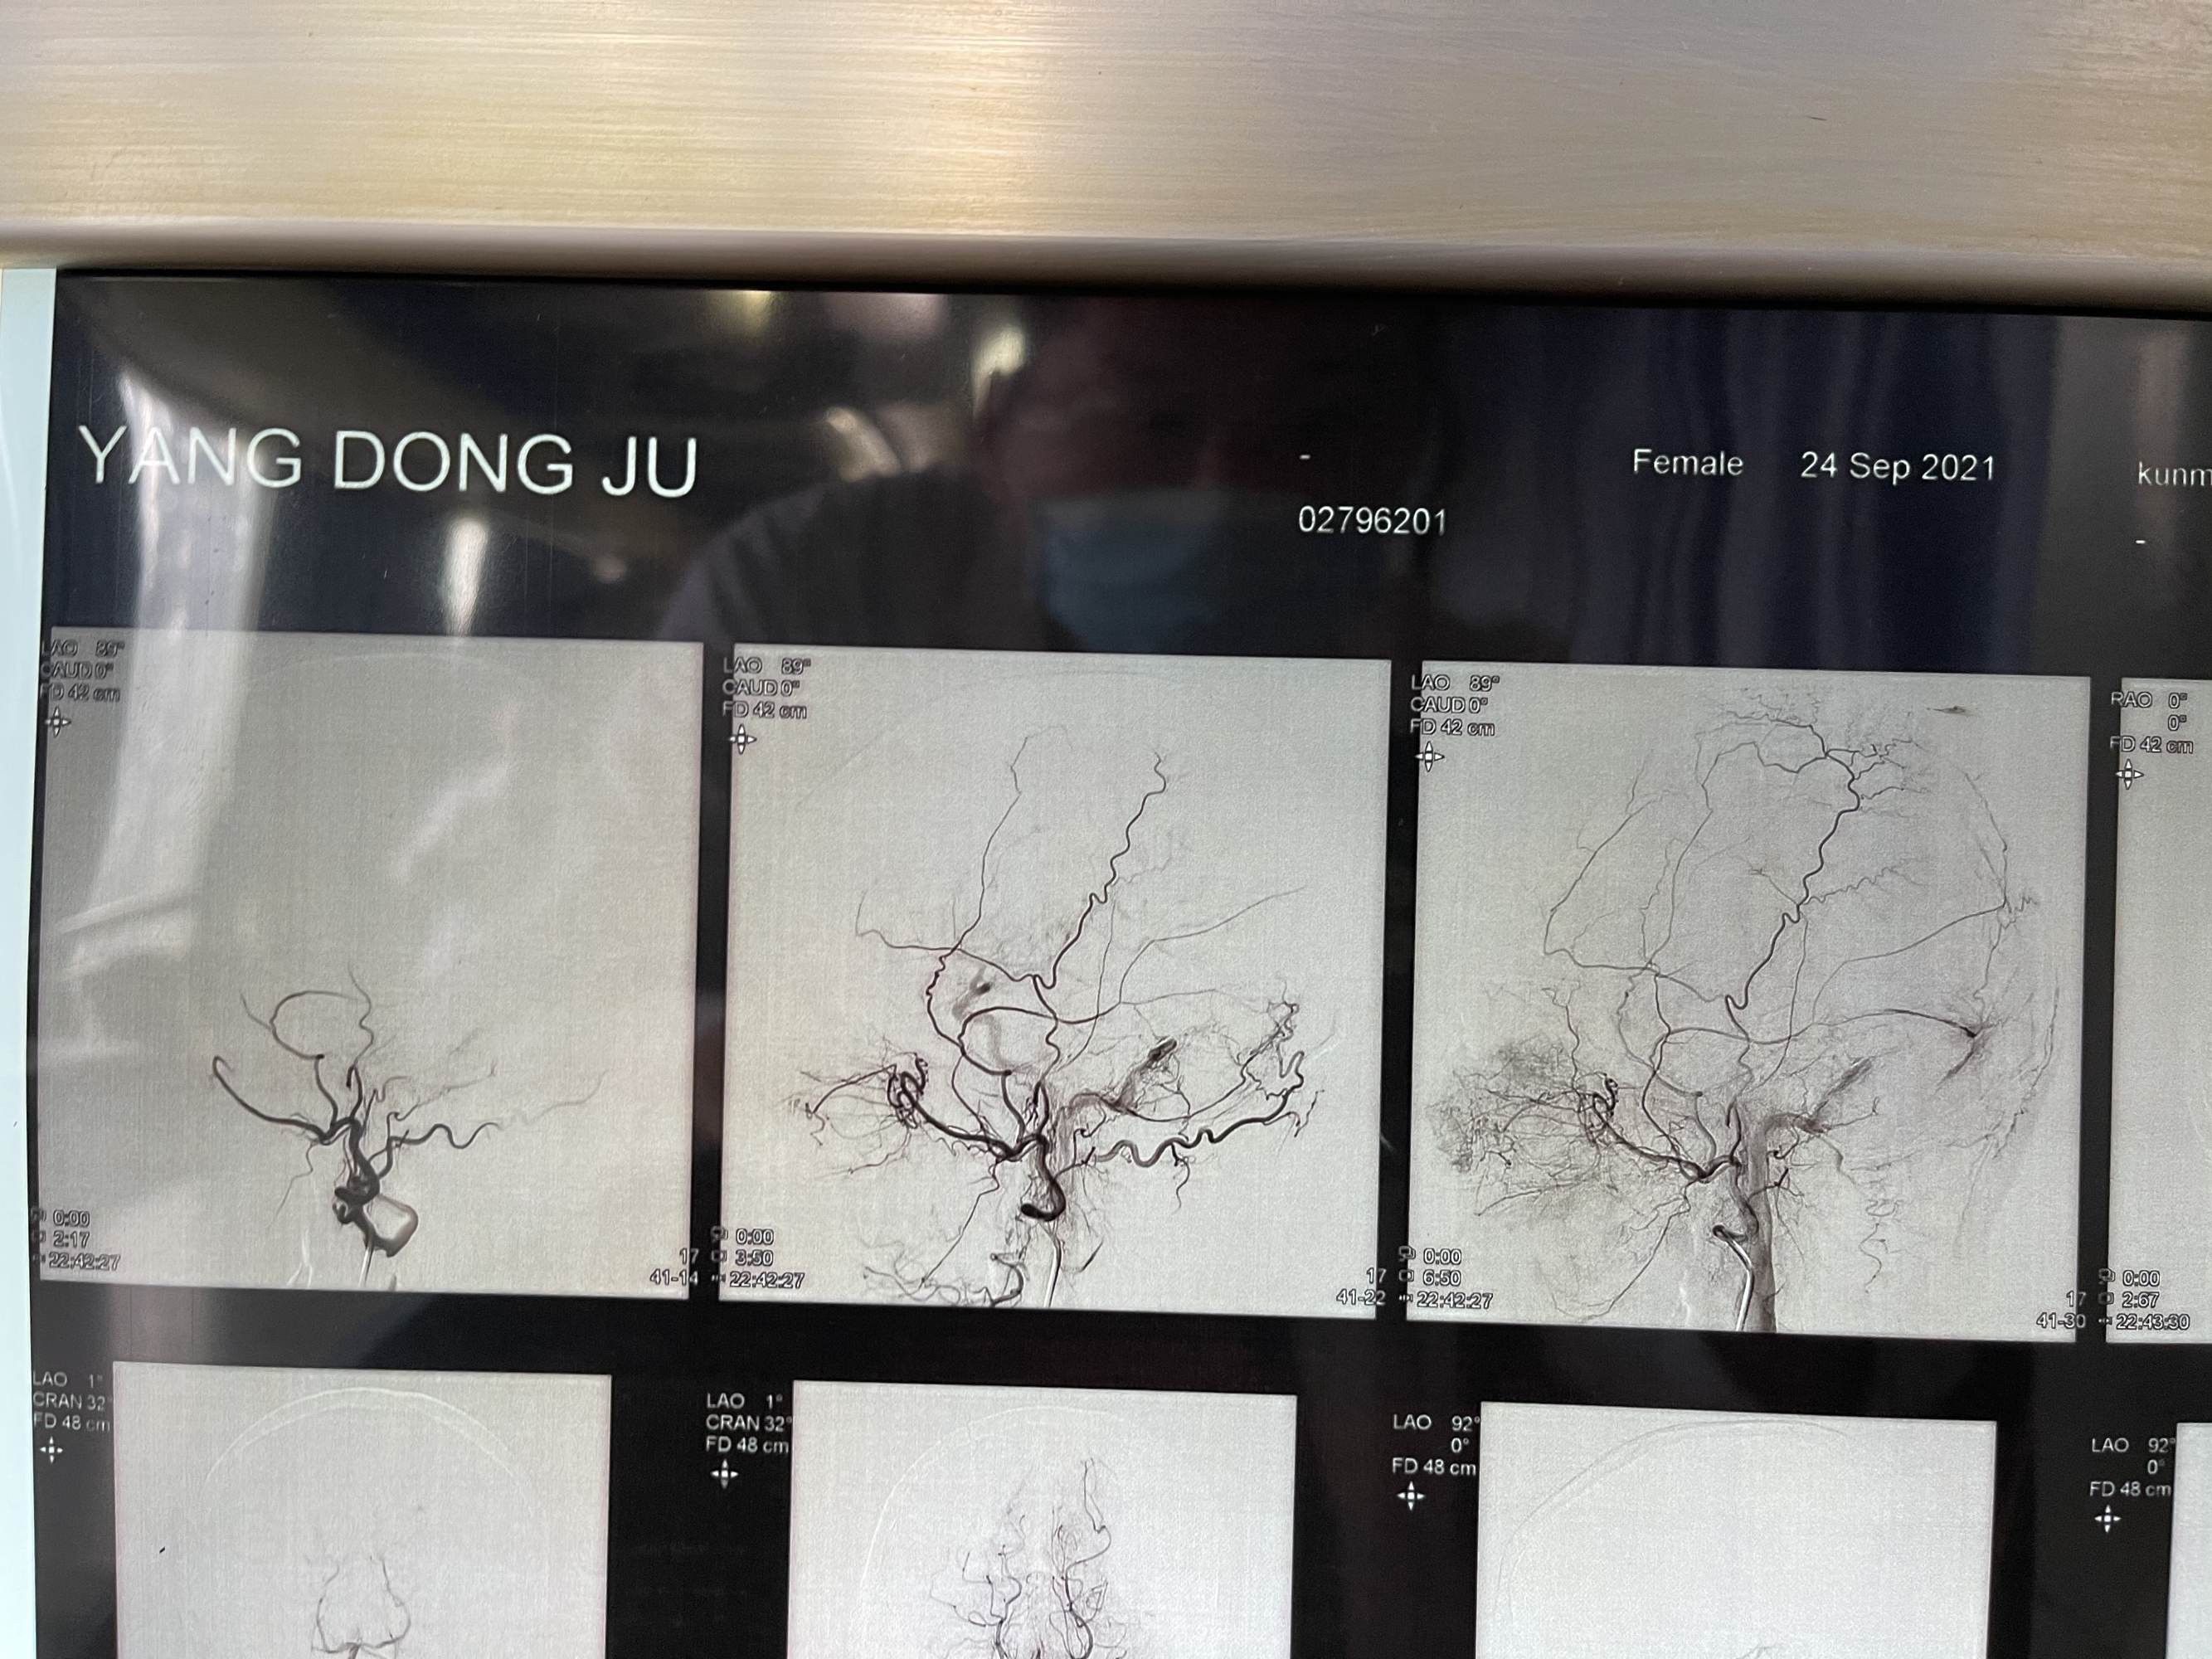

患者女性,68岁,头痛入院,行造影检查硬脑膜动静脉瘘,双侧脑膜中及枕动脉主要供血,开口位于枕部,皮层引流静脉代偿性粗大,拟介入栓塞

看看术前造影,迂曲的静脉,上矢状窦后三分之一及横窦已经不显影了

患者女性,68岁,头痛入院,行造影检查硬脑膜动静脉瘘,双侧脑膜中及枕动脉主要供血,开口位于枕部,皮层引流静脉代偿性粗大,拟介入栓塞

看看术前造影,迂曲的静脉,上矢状窦后三分之一及横窦已经不显影了